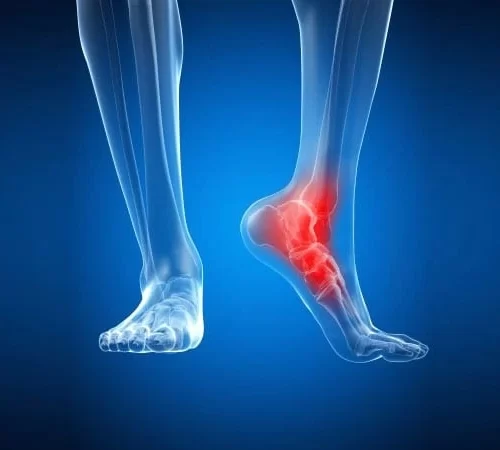

Ayak ve Ayak Bileği Cerrahisi